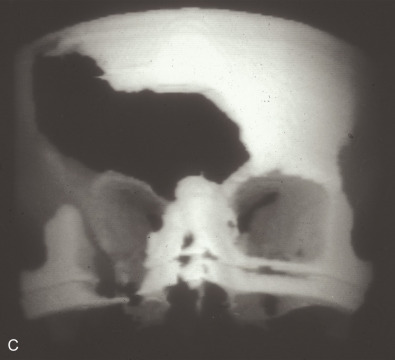

Just before his first birthday this boy was bitten by a Boxer dog and sustained a loss of most of his right parietal bone, dura, and a good bit of parietal lobe ( Fig. 3.1.1 ). Excellent neurosurgical care debrided nonvital brain and repaired the dura with an artificial dural substitute. Because of the lack of native dura, spontaneous regeneration of the bone was unlikely. Three months later, at 14 months of age, a switch cranioplasty was performed, taking the entire left parietal bone to replace what was missing on the right. This left the left side devoid of bone, but with healthy dura and pericranium. Several fragments of his skull, which had been saved and frozen from the original operation, along with a large segment of rBMP-2 impregnated in collagen sponge, were placed between the dura and the pericranium. At 2 years of age the boy had an intact skull and only a mild left hemiplegia.